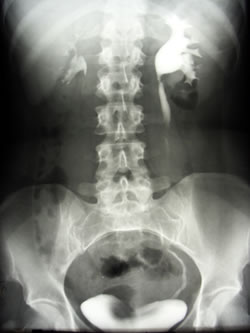

Современные методы урографии: визуализация здоровья